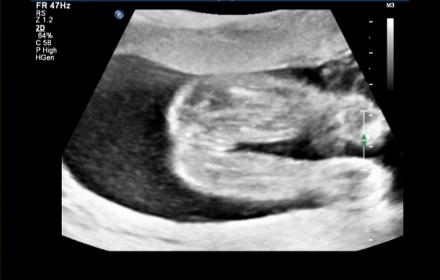

Attachment 7657 13 week nub shot